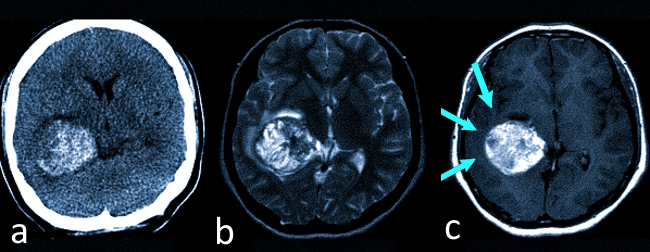

Кавернозная ангиома на КТ (А) и МРТ (В, С — указаны стрелками).

Процесс постановки диагноза “сосудистая мальформация головного мозга” зачастую является сложной задачей. Неосложненные ангиомы небольших размеров на компьютерной томографии обнаружить сложно, особенно без применения контрастного вещества. Магнитно-резонансная томография в некоторых случаях может предоставить более полную информацию, так как данный метод более чувствителен к изменениям в скорости кровотока.

Компьютерную томографию используют в экстренных ситуациях для диагностики внутримозговых кровоизлияний. Крупные ангиомы часто выявляются случайно в процессе других исследований.

МРТ применяется для наблюдения за динамикой сосудистых мальформаций и как дополнительный метод визуализации для выбора наиболее подходящей стратегии лечения.